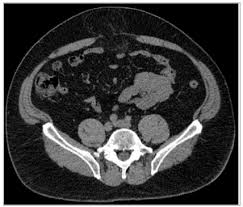

More important CT findings can be used to diagnose unsuspected hernias and to distinguish hernias from masses of the abdominal wall such as tumors hematomas abscesses undescended testes and aneurysms. Cross-sectional CT scans can show hernias and the contents of the peritoneal sac. No advice on which is better but I will tell you my experience.

Ct Scan Of A Patient With A Large Incisional Hernia The Hernia Download Scientific Diagram